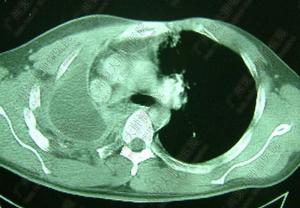

精原細胞瘤 後前位 側位20%-30%的病人無症狀,有症狀的病人症狀為胸痛、咳嗽、呼吸困難、咯血等,可以有嗜睡、體重減輕。10%~20%病人出現上腔靜脈梗阻綜合徵。這些臨床症狀常與腫瘤對縱隔結構的壓迫、侵犯有關。一部分精原細胞瘤生長在氣管內,並局部擴展至鄰近的縱隔和肺。一般縱隔精原細胞瘤經淋巴途徑轉移播散,亦可發生血行轉移,骨骼和肺臟是最常轉移的部位。

胸片多見巨大前縱隔腫瘤,有時可以發現腫瘤沿氣管內生長。CT多為密度均勻的大包塊,50%可見胸內轉移或擴展超出前縱隔而不能手術。CT和MRI有助於確定腫瘤的範圍、對縱隔結構的侵犯情況。首次就診切除率低於25%。

應對所有患前縱隔腫瘤的年輕男性測定血α-FP、β-hCG水平。單純的精原細胞瘤幾乎均無AFP、hCG的升高,7%-10%有hCG升高,但常不超過100ng/ml,AFP不升高。

CA125也可能為生物學標記。腫瘤組織的染色體分析可發現12號染色體上特徵性等臂染色體,這對鑑別生殖細胞腫瘤和其他類型的腫瘤有助。